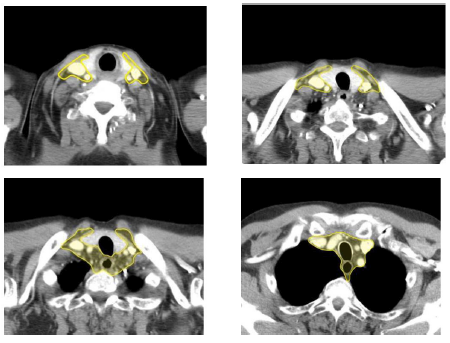

Contouring atlas: the elective lymph nodes

Supraclavicular lymph nodes are analogous to level 4 in head and neck cancers2. The cranial border is defined by the cricoid cartilage. The anterior borders correspond to the sternocleidomastoid muscles. Cranially the posterior border is the posterior edge of the sternocleidomastoid muscle. Caudally the posterior border is the anterior edge of the scalenius muscles and the apex of the lungs. The medial limit is the medial edge of the common carotid artery. The lateral limit is defined by the lateral edge of the sternocleidomastoid muscle cranially and the lateral edge of the scalenius muscles caudally. The inferior border extends into the thoracic inlet.